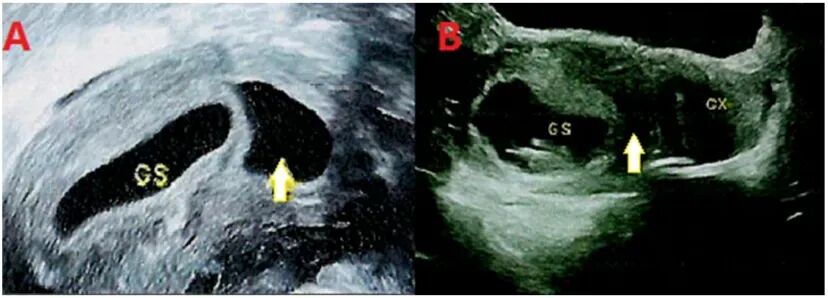

在上述产前检查案例中,通过回溯孕早期超声记录,研究者发现这名孕妇在孕7-9周时,子宫内曾出现短暂的“无回声区”,随后消失——这被推测是“消失的双胞胎”的残留痕迹,孕妇最初怀的异卵双胎在极早期融合,形成了携带两套基因组的嵌合体胎儿。